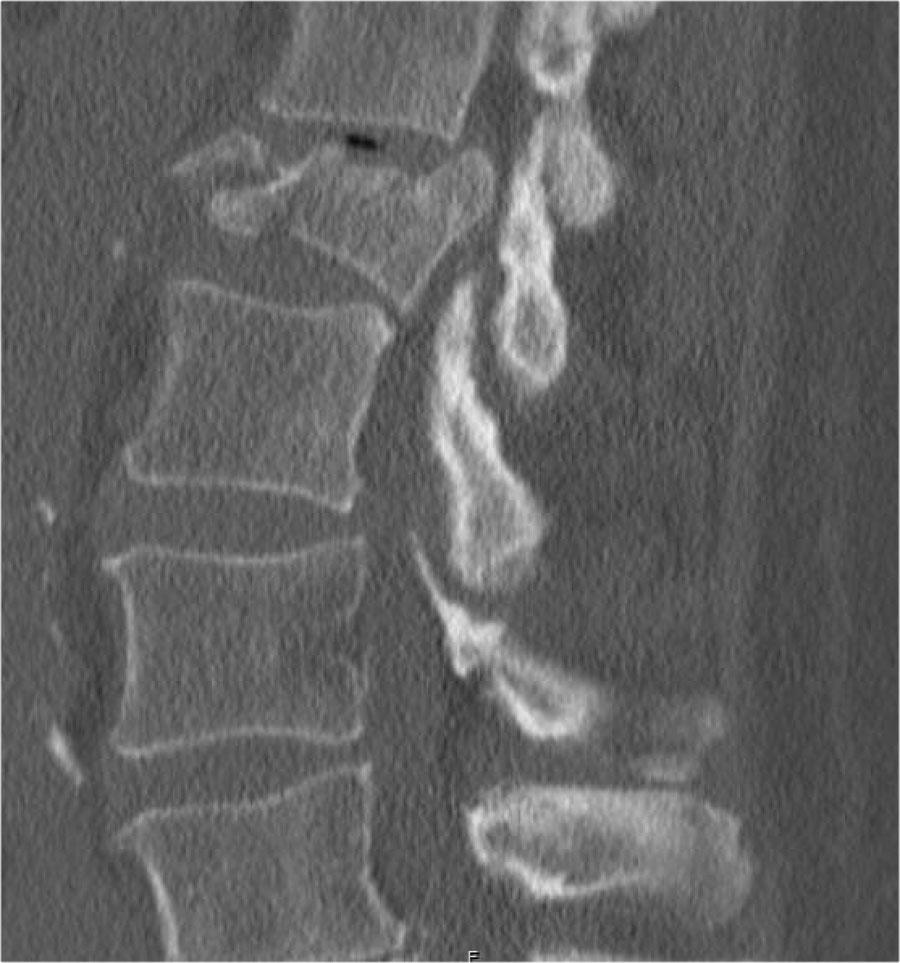

Cột sống cứng

Bệnh nhân có cột sống cứng (như trong viêm cột sống dính khớp, DISH và viêm khớp dạng thấp) dễ bị gãy xương cột sống hơn, ngay cả sau chấn thương nhẹ (6).

Vôi hóa dây chằng cột sống và vôi hóa vòng sợi thay đổi cơ sinh học của cột sống, tạo ra các cánh tay đòn dài và hạn chế khả năng hấp thụ ngay cả các va chạm nhỏ.

Xương thường rất loãng.

Các hình ảnh là của một bệnh nhân với hình ảnh cột sống tre điển hình do viêm cột sống dính khớp.

Sau khi ngã ngửa, không thấy gãy xương trên phim X-quang.

Tuy nhiên, CT cho thấy một đường gãy mảnh qua mặt trước thân đốt sống và cả qua mỏm gai.

Tiếp tục xem các hình ảnh MRI.